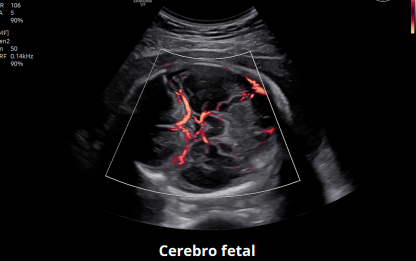

MV-Flow™ y LumiFlow™

Estas tecnologías permiten la visualización de flujo microvascular en 3D y flujos sanguíneos lentos, esenciales para estudios fetales y ginecológicos. MV-Flow™ muestra la intensidad del flujo microvascular en color, mientras que LumiFlow™ ofrece una representación tridimensional del flujo sanguíneo, ayudando a comprender la anatomía vascular de manera intuitiva.